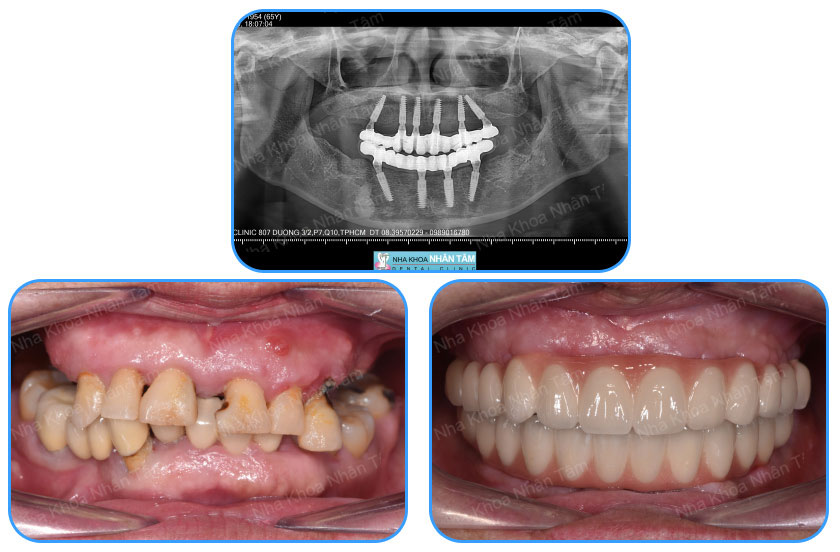

Trồng răng Implant all on 4 khôi phục hoàn hảo tính thẩm mỹ của hàm răng